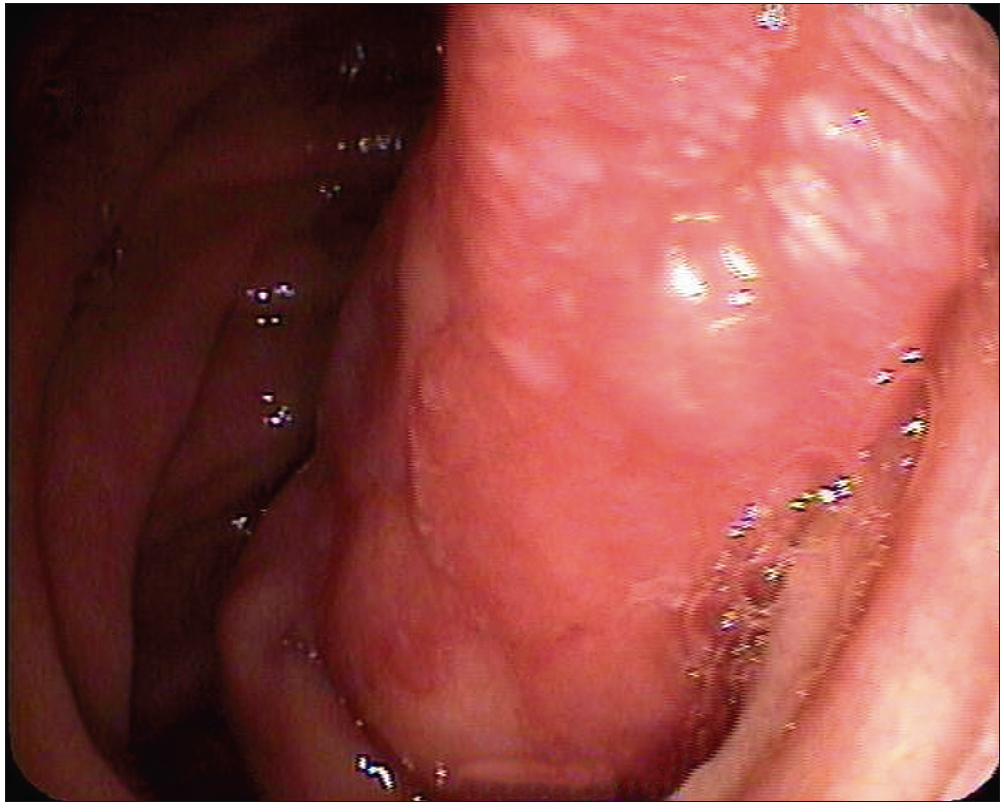

Paciente masculino de 56 años de edad, que consultó por melena de 48 horas de evolución. Ingresó hemodinámicamente estable con una hemoglobina de 9,2 g/dl (valores previos de 13,1 g/dl). Como antecedentes refirió dos episodios previos de hemorragia digestiva alta a los 54 años de edad, que fueron estudiados en otra institución sin encontrar la causa del sangrado. Se realizó una videoendoscopía digestiva alta que evidenció una lesión polipoidea subpediculada de superficie erosionada de aproximadamente 5 cm, ubicada en la tercera porción duodenal. (Figura 1 y 2).

Figura 2. VEDA. Lesión polipoidea subpediculada de aproximadamente 5 cm que emerge

hacia la tercera porción duodenal